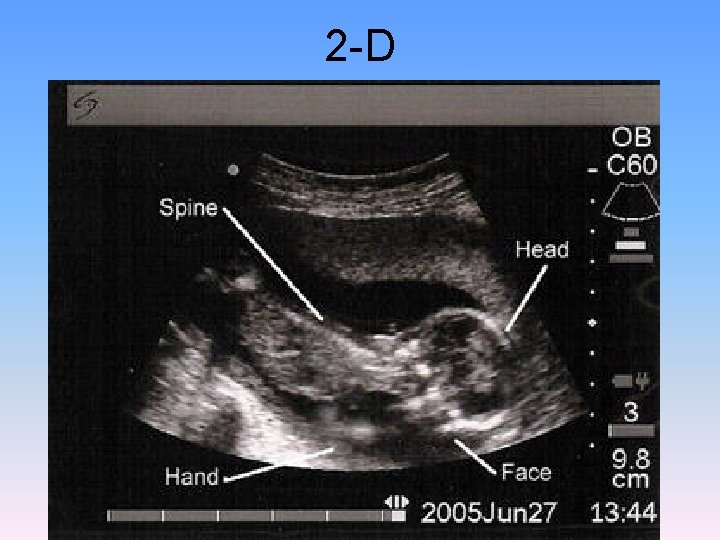

2 -D